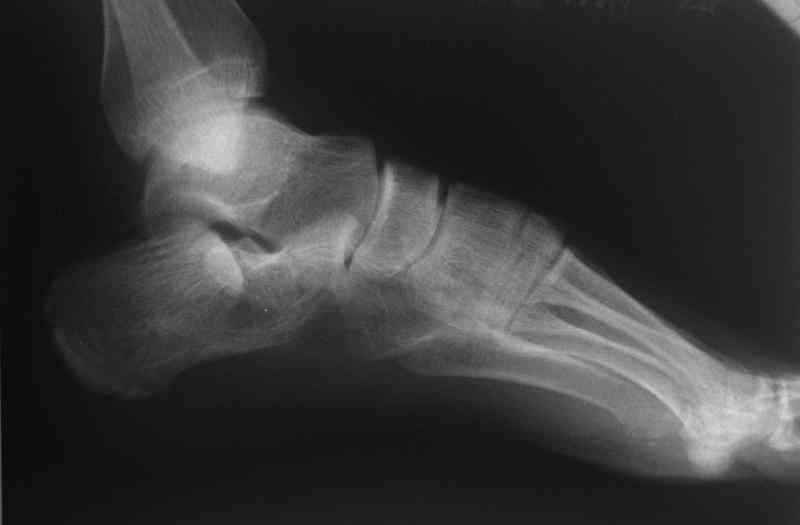

Открытый и закрытый способы лечения.